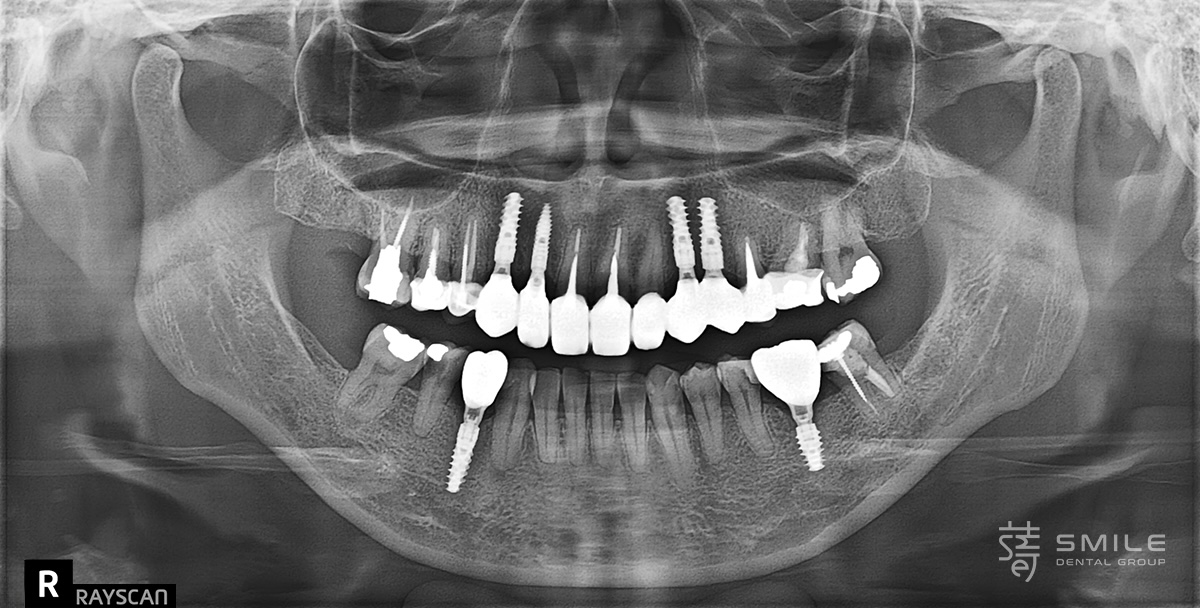

第三階段 X-Guide導航植牙,精準安全

Stage Three: Precision and safety with X-Guide navigation

此階段導入 X-Guide 藍光導航系統,結合 3D 影像即時導引,精準掌握植體深度與角度,並同步追蹤手術位置,大幅提升安全性與準確度。 對骨條件複雜、需多點植牙的患者尤其重要。

For the implant placement, the X-Guide dynamic navigation system was introduced. Combining 3D imaging with real-time tracking, it allowed precise control over implant depth and angle while continuously monitoring surgical position.

This level of precision is particularly vital for patients with complex bone structures or those requiring multiple implants, ensuring a safer and more predictable outcome.

瑞士頂級植體,締造長久穩定笑容

Swiss Premium Implants: Crafting a Lasting, Stable Smile

紀醫師為陳太太選用 Straumann® 士卓曼植體,結合 Roxolid® 高強度材質與 SLActive® 親水表面技術,加速骨整合、縮短癒合期,降低植體周圍炎風險。

此技術相當適用於即拔即植、大範圍重建等複雜手術,是追求長期穩定與自然美觀的首選。

Dr. Ji selected premium Swiss Straumann® implants for Mrs. Chen, renowned for their exceptional stability and long-term durability.

The implants use Roxolid® high-strength alloy, providing robust support even with limited bone, and feature SLActive® hydrophilic surfaces that speed up bone integration, shorten healing time, and reduce Peri-implantitis risk.

This technology is especially suited for immediate placement or extensive full-mouth reconstruction, ensuring long-lasting stability and natural aesthetics.